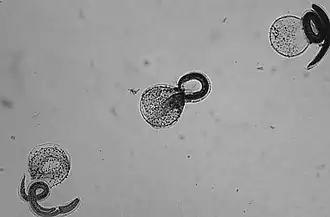

Vajíčka jsou produkována červem ve střevě mývala, uvolněná vajíčka dozrají do infekčního stavu externě v půdě. Při požití infikovaného vajíčka se vylíhnou larvy, které se dostanou se do střeva hostitele.[3] Mohou pak ale migrovat do dalších orgánů včetně mozku.

Dospělá škrkavka žije a rozmnožuje se ve střevě svého definitivního hostitele, mývala. Samice škrkavky může produkovat 115 000 – 179 000 vajíček denně. Vylučují se spolu s výkaly a po 2–4 týdnech se v půdě stanou infekčními. Při požití jiným mývalem se životní cyklus opakuje.

Pokud však vajíčka pozře mezihostitel (malí savci, ptáci), larvy B. procyonis proniknou jeho střevní stěnou a migrují do tkání. Larvy mají tendenci migrovat do mozku, způsobovat zde škody a ovlivňovat chování mezihostitele, což z něj pro mývaly dělá snazší kořist.